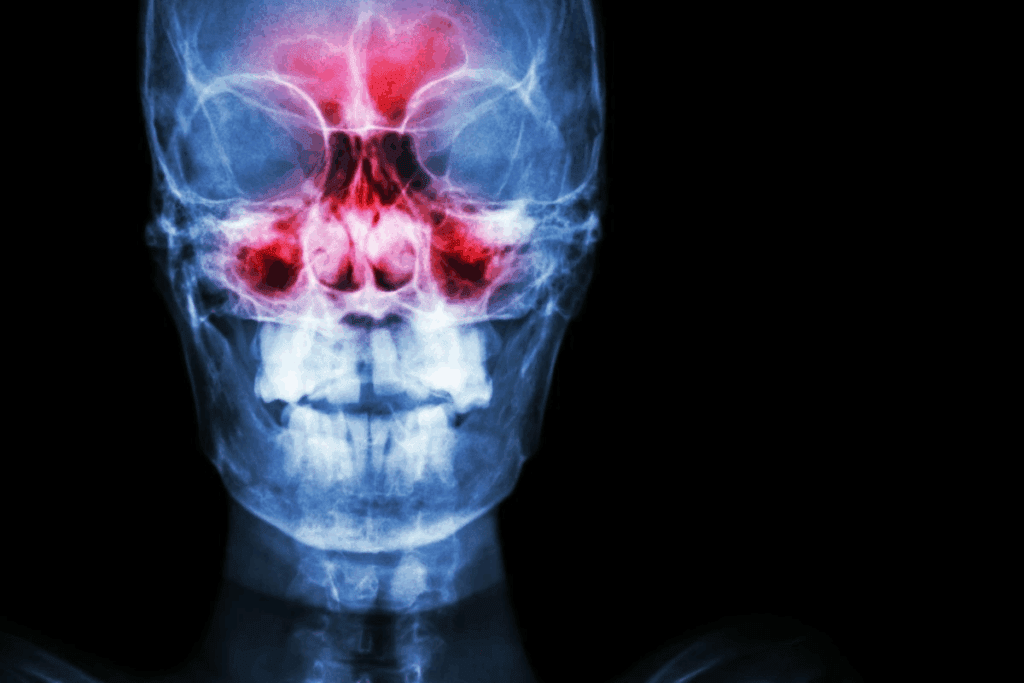

Feeling dry nasal passages can be really uncomfortable. It can mess up your daily life. When our sinuses don’t have enough moisture, they get irritated. This can lead to bigger problems if not treated.

The sinuses are around the forehead, cheeks, and nose. They have a thin layer of mucus that keeps them moist. This mucus traps dust, bacteria, and other pathogens, stopping them from reaching the lungs. Knowing how healthy nasal mucous membranes work is key to understanding dry nasal passages.

Moisture balance is key for the sinuses to work right. If the nasal passages are too dry, the mucus becomes thick and sticky. This makes it hard to trap pathogens, leading to issues like:

Untreated dry sinuses can lead to serious health problems. They become more likely to get infected. The lack of moisture causes chronic inflammation and discomfort.

Dry sinuses are more likely to get infected. This is because the body’s natural defenses are weakened. Dry mucous membranes can’t trap pathogens well, making infections more common.